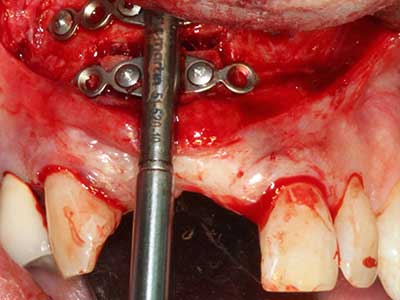

Fig. 18: Preparación de una tapa cortical con la sierra ósea piezoeléctrica (Piezomed, W&H).

Fig. 20: La tapa ósea extraída se readapta y se fija mediante un tornillo para osteosíntesis (KLS Martin, Tuttlingen).